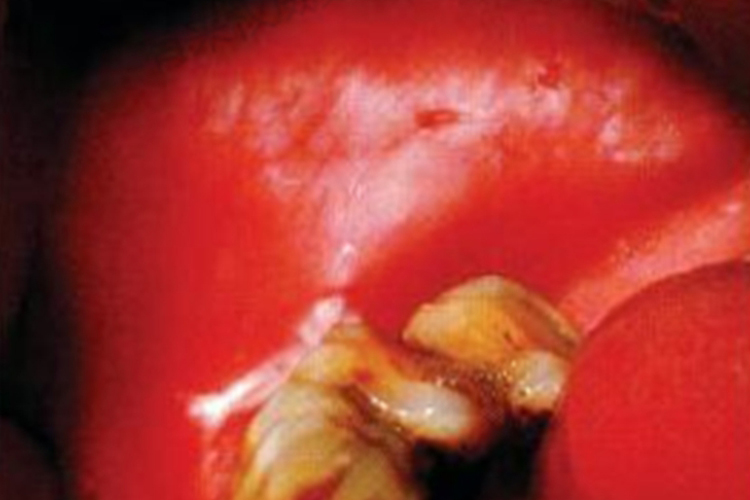

白角化症可发生在口腔黏膜的任何部位,以颊唇、舌部多见为灰白色或乳白色的边界不清的斑块或斑片,不高出或略高于黏膜表面平滑、基底柔软无结节。与周围正常的黏膜相比,白角化区域黏膜的质地及弹性没有明显的变化。组织学上为良性的单纯过角化。

由长期的机械性或化学性刺激所引起以残根、残冠、上下颌后牙的锐利边缘、错位咬合、不良修复体或吸烟等刺激因素最为常见。